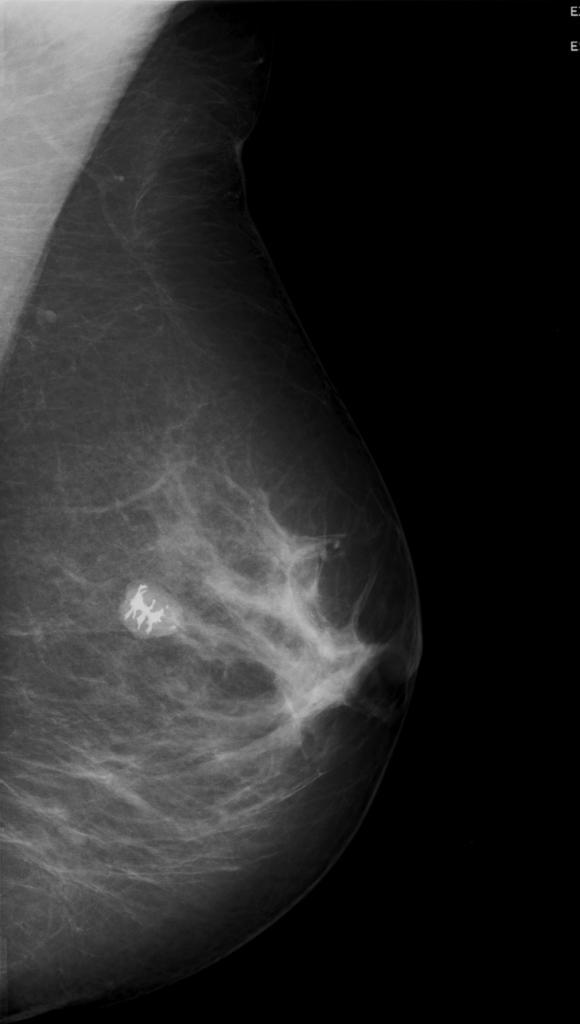

Linear, thick, ‘rod-like’ calcifications in both breasts, with a symmetrical distribution. Typical appearance of plasma cell mastitis (BI-RADS 2, benign).

Predominantly fatty breast tissue. No further findings.

Mammography

Plasma cell mastitis has a characteristic appearance. Calcifications are thick, linear, rod-like or cigar-shaped. Calcifications can be up to 10 mm long. They tend to be bilateral, often symmetrical in distribution and oriented with long axes pointing toward the nipple1. Branching may sometimes be seen.

Compared to microcalcifications of DCIS or ductal carcinoma, calcifications of plasma cell mastitis are larger in both length and caliber and have a smoother outline.